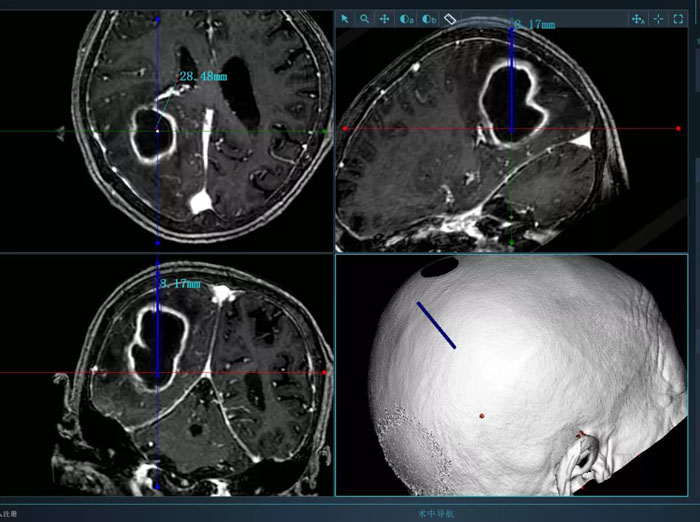

病例2.患者為74歲老年女性,術(shù)前因高熱入院,檢查發(fā)現(xiàn)腦膿腫。該患者體質(zhì)較差,而且膿腫體積大,形態(tài)不規(guī)則,傳統(tǒng)穿刺引流方式難以完全將膿腫引流徹底,且易造成膿腫擴(kuò)散,引起嚴(yán)重不良后果。續(xù)繼軍主任決定采用智能機(jī)器人輔助穿刺,術(shù)前借助智能機(jī)器人手術(shù)計劃系統(tǒng)避開腦重要功能區(qū)及血管,精心設(shè)計了最優(yōu)穿刺路徑。續(xù)繼軍主任帶領(lǐng)丁鵬主治醫(yī)師在機(jī)器人引導(dǎo)下行膿腫穿刺引流,一次穿刺到位,術(shù)中引流出腦膿腫25ml。術(shù)后,復(fù)查CT顯示引流管到達(dá)預(yù)定靶點,位置良好,膿腫引流滿意,患者顱高壓癥狀明顯緩解,腦膿腫得到有效控制。